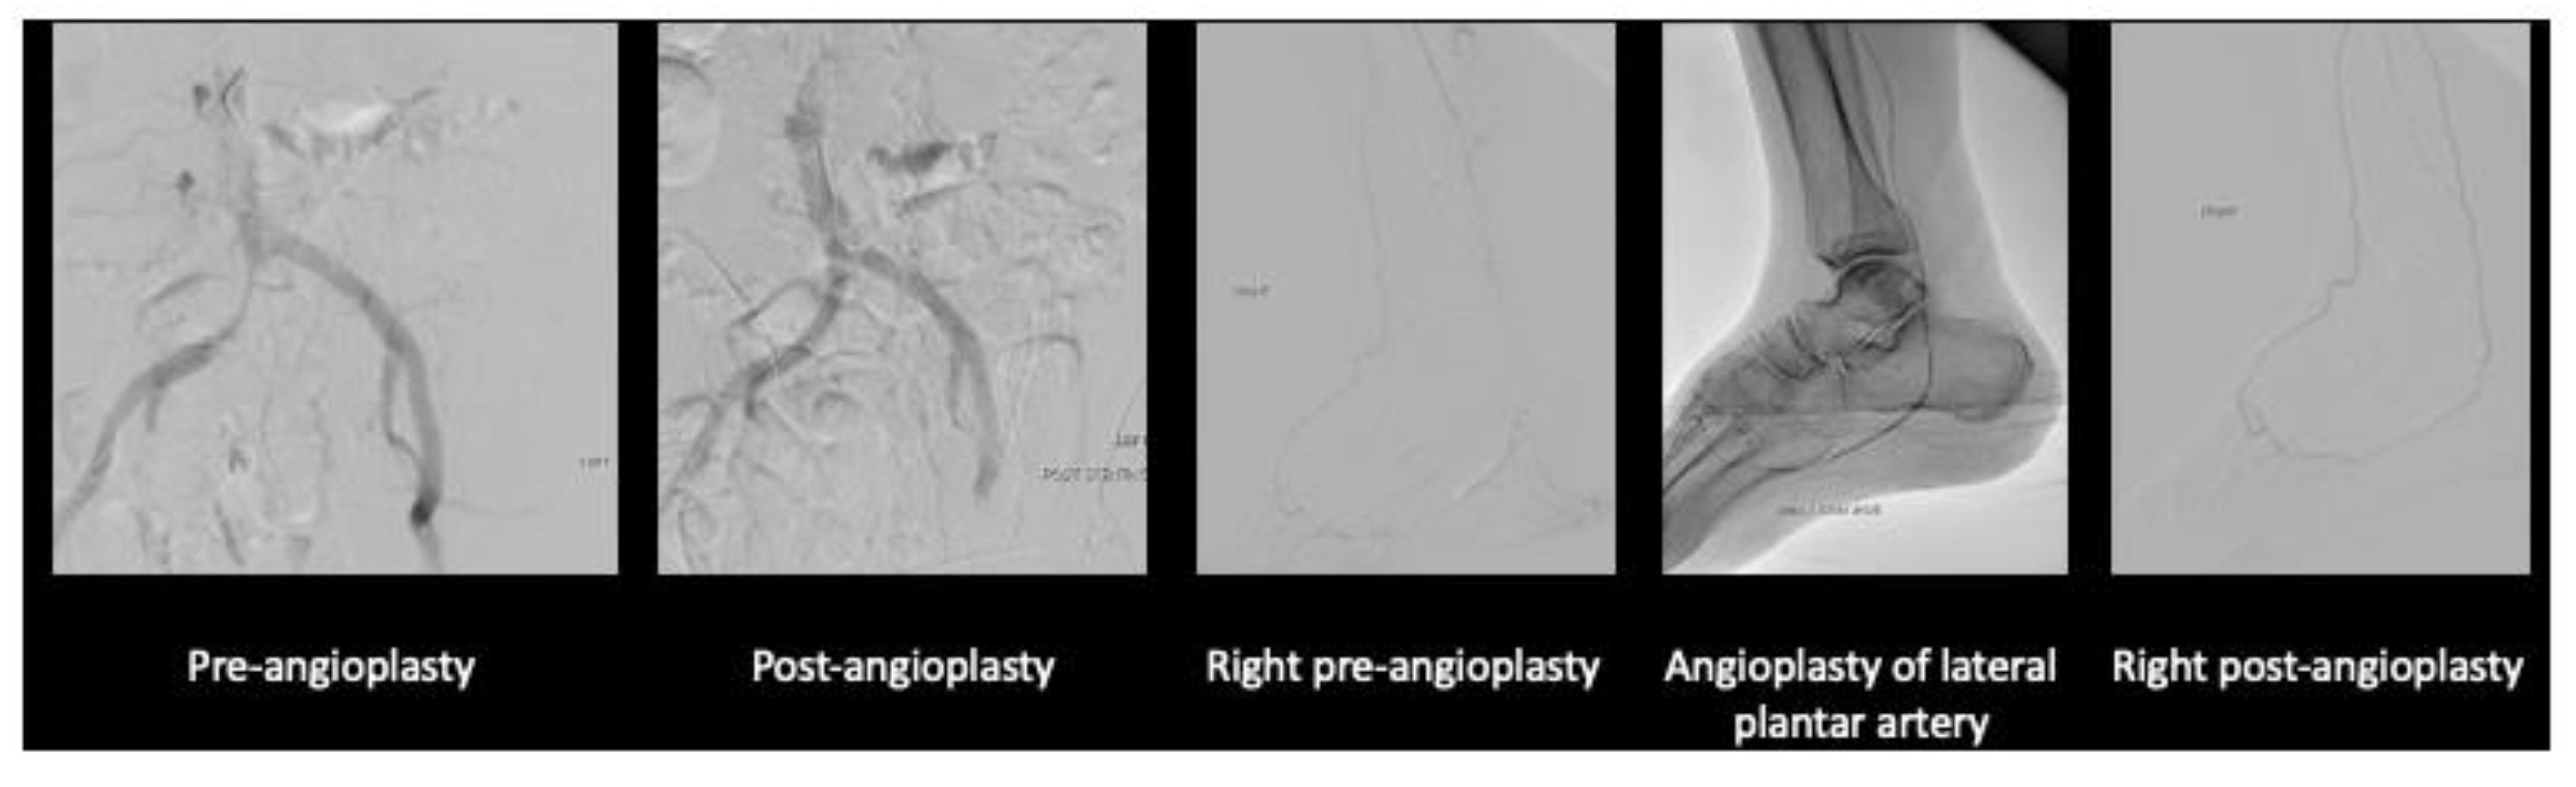

After much discussion, patient and vascular team decided to attempt limb salvage with bilateral lower limb angioplasties and fifth toe ray amputations at the same setting. Angioplasty to anterior tibial artery, posterior tibial artery, dorsalis pedis, common plantar artery was performed on the right lower limb with successful outcome. On the left lower limb, angioplasty to the anterior and posterior tibial artery was performed. Patient’s wound recovered with combination of culture directed antibiotics, vacuum dressing and motivation from a supportive family.

Figure 3. Angioplasty images of the left lower limb.